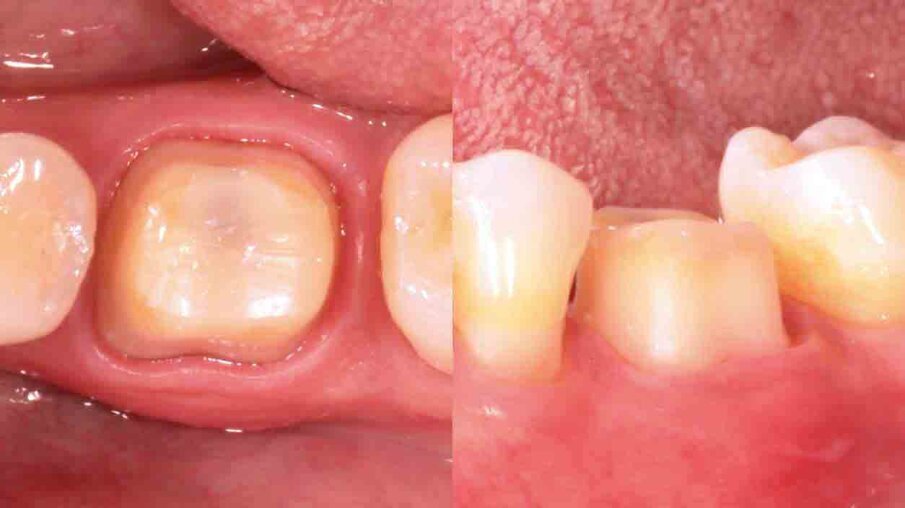

Fig. 3: Upon removal of the old filling, it becomes clear that a crown is needed to ensure the required stability. The tooth is built up with 3M™ Filtek™ Bulk Fill Posterior Restorative, which may be placed in conjunction with 3M™ Single Bond Universal Adhesive and in increments of up to 5 mm.

Fig. 4: Following tooth preparation, a temporary crown is produced chairside with 3M™ Protemp™ 4 Temporization Material. This material exhibits a high strength and a natural gloss without polishing.